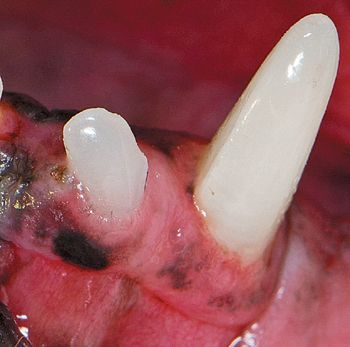

Evaluation and treatment of these all-too-common oral defects.